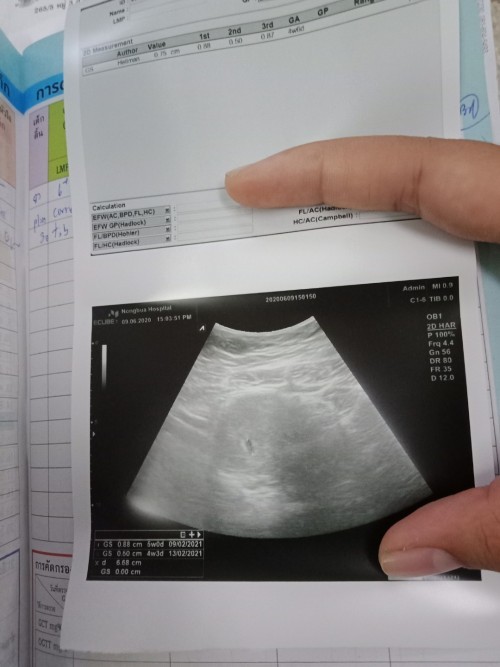

6w 5dคะ